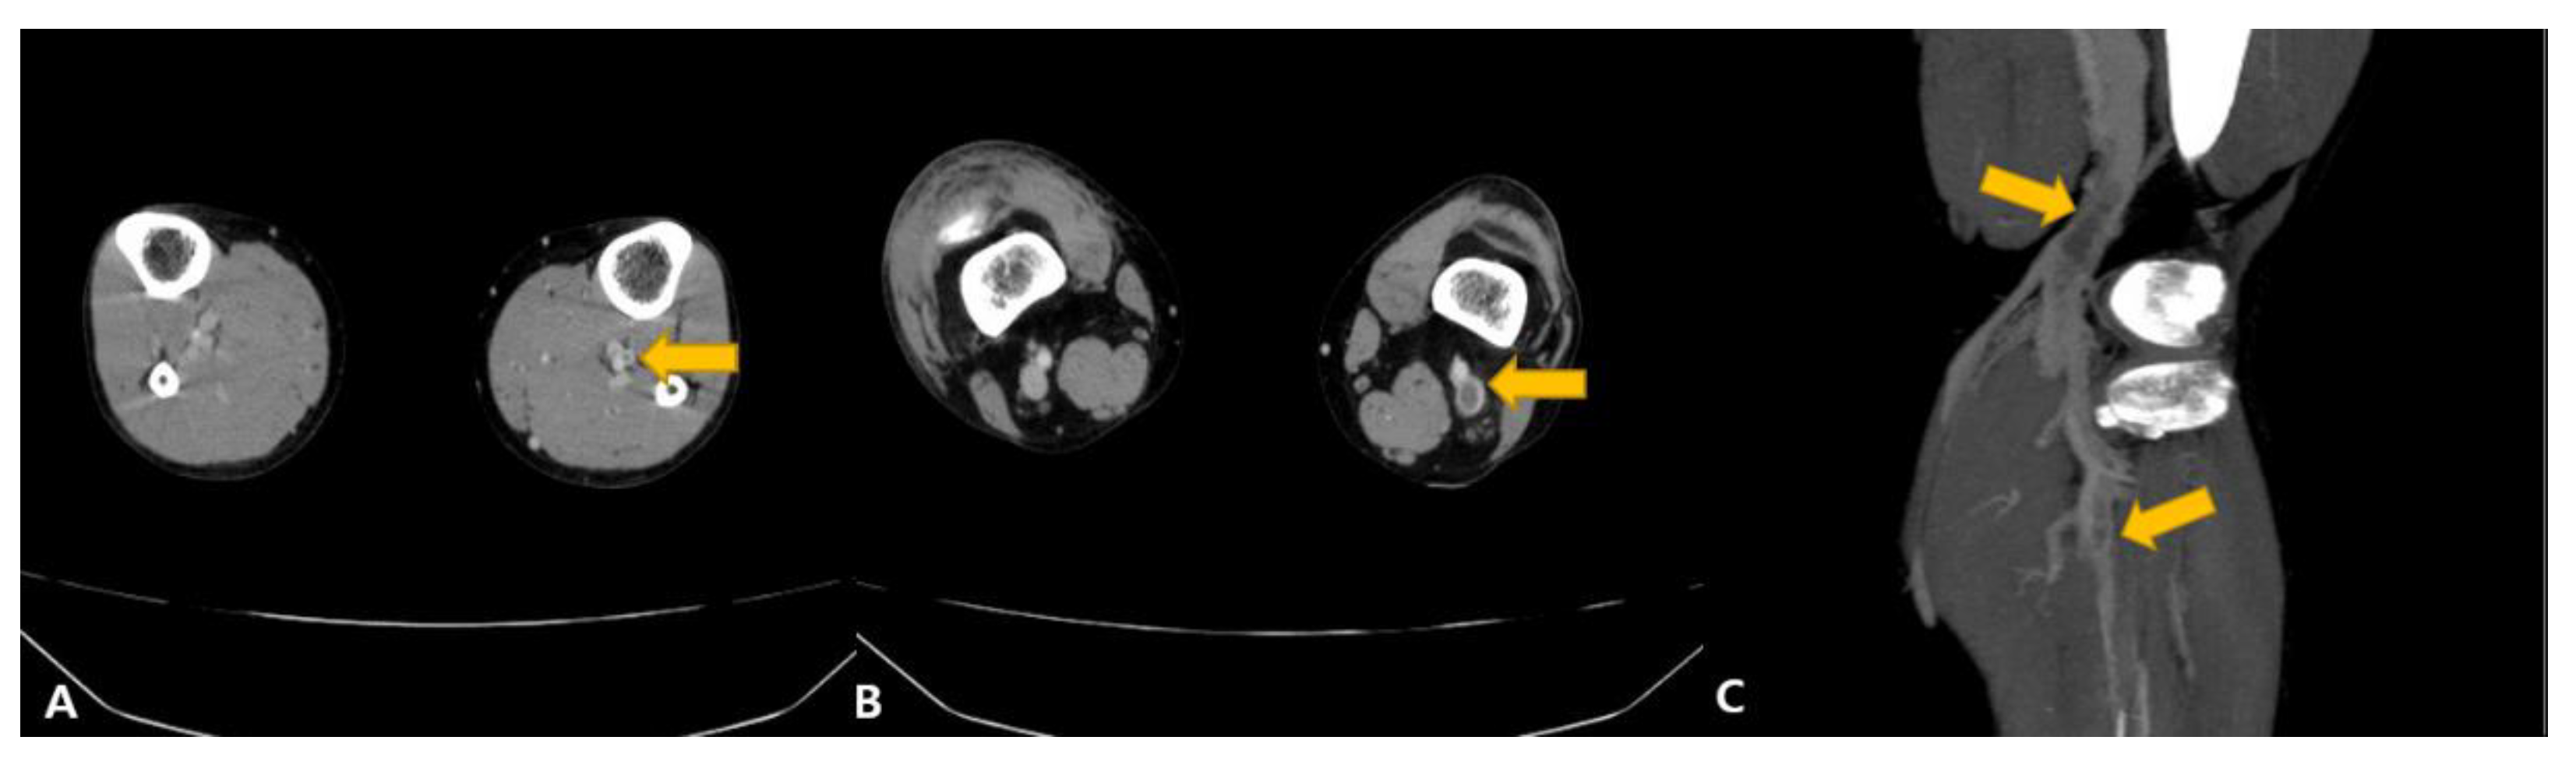

2. Case Presentation